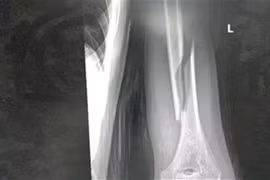

1 tuần 3 trường hợp gãy xương cánh tay từ trò chơi vật tay

Có những trường hợp nhập viện trong tình trạng gãy nham nhở, khó đưa xương về vị trí ban đầu, tổn thương các dây thần kinh quay, trụ và mạch máu lân cận.

Trong lúc thi vật tay cùng bạn bè, nam thanh niên 18 tuổi bất ngờ nghe thấy một tiếng “rắc” vang lên, kèm theo cảm giác đau dữ dội.